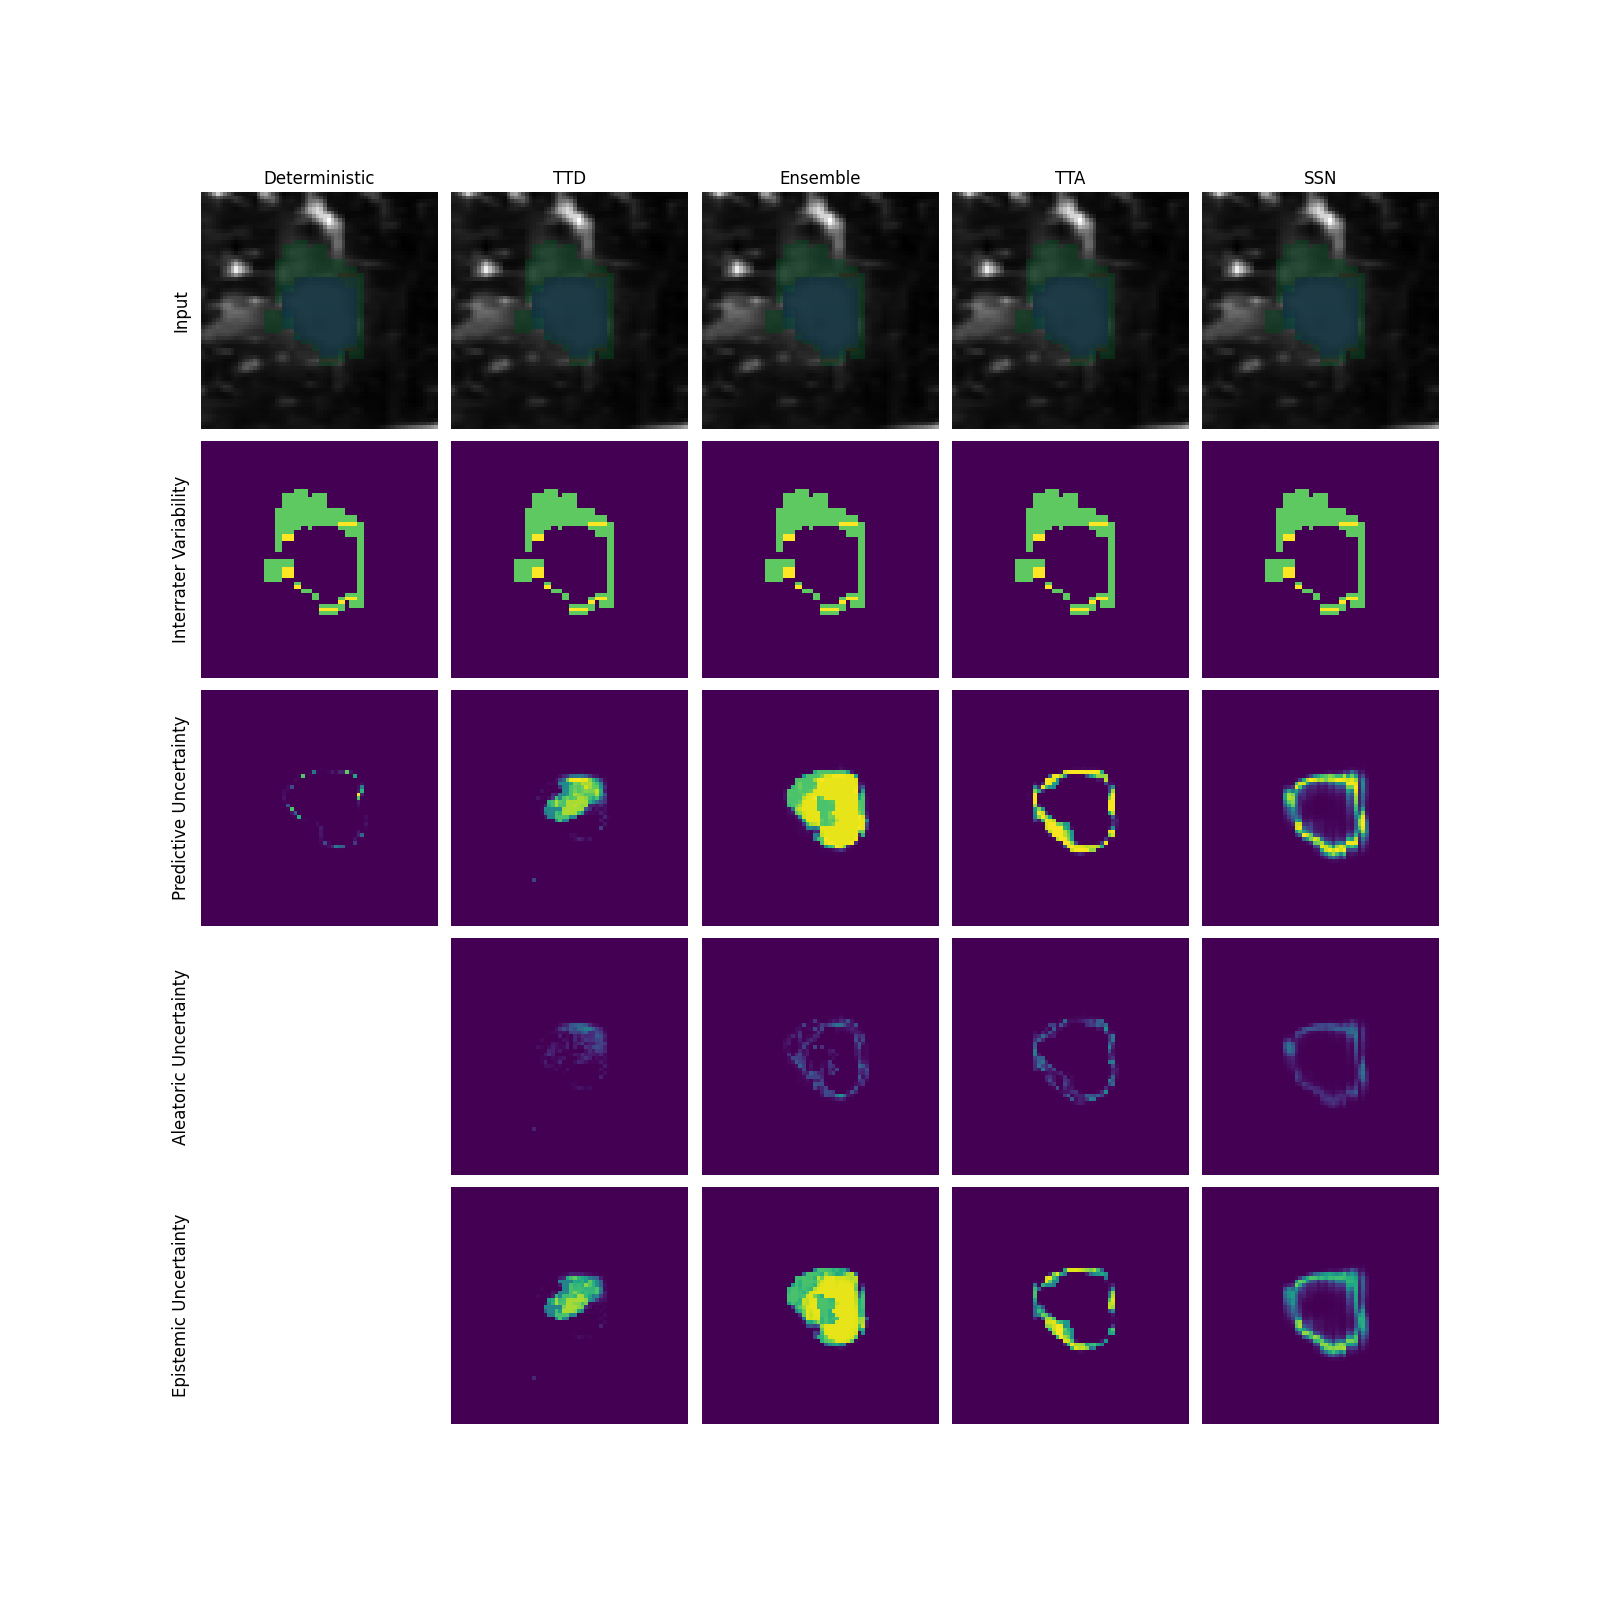

Q1 + Q2: For assessing the capability of uncertainty methods in capturing AU, we employ the normalized cross-correlation (NCC) as a quantitative measure between the predicted uncertainty map and the reference uncertainty map based on the disagreement of multiple raters (for details see Appendix A). Additionally, we perform qualitative inspections of the uncertainty maps. Based on the theory, successful separation of uncertainties would imply AU-measures to exhibit high NCC and high qualitative fidelity (Q1 = ”yes”) and vice versa for EU-measures (Q2 = ”no”).

The general findings of the uncertainty separation study are summarized in Figure 2a, while underlying results are shown in Figure 2b for the toy dataset and Figure 3 (see gray-shaded ”Q” indicators on respective panels) for LIDC and GTA5/CS. More detailed descriptions and results as well as a qualitative analysis of uncertainty maps are provided in Appendix G.

Modeling aleatoric uncertainty (Q1 + Q2) While AU-measures clearly captured AU much better than EU-measures for the toy dataset, this behavior is inconsistent on the real-world datasets. On the LIDC datasets with AU stemming from rater ambiguity, which mostly occurs at the border of structures, the benefit of separating AU-measures from EU-measures is not evident when examining the NCC scores. For GTA5/CS, where induced label ambiguities span entire spatial structures, the AU-measures generally capture AU better than EU-measures. However, the absolute NCC scores from the AU-measures vary greatly across prediction models. We attribute this to SSNs capturing the widespread label ambiguities, while other models overemphasize the border regions.

Toy dataset. In the toy dataset analysis, AU uncertainty measures have generally higher NCC values compared to EU uncertainty measures, indicating a successful separation of AU and the highlighting of relevant areas (Q1) which is also supported by the qualitative analysis with high uncertainty signals in areas with rater disagreement (see Sec. G.3). Meanwhile, the EU-measures perform worse than PU and AU measures indicating that EU-measures do not measure AU. An exception to this finding are SSNs, where NCC scores are higher for EU-measures compared to other prediction models. This discrepancy may be attributed to the presence of AU at the border regions which is not explained by the variability variable.

LIDC datasets. On the LIDC datasets, EU-measures performance is similar to that of AU-measures. Therefore the approaches seem to model EU in the areas attributed to AU (Q2).

In fact, for SSNs, the AU-measure even shows a lower NCC than the EU-measure, which could be attributed to the SSNs rating the border regions with high EU, which are the regions of disagreement.

The qualitative analysis indicates that a slightly better separation between AU and EU becomes apparent when there is meaningful inter-rater variability beyond small border regions (see Figure 10).